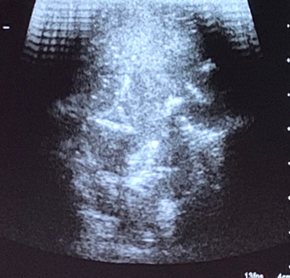

化学消融属于局部化疗方案,操作医疗器械吸收治疗药品,注射入肿瘤后逐日缓释吸收的治疗药品,降低治疗药品的系统毒性。

· 适合体积較小 (长边小於 4cm)且不规则形状的肿瘤